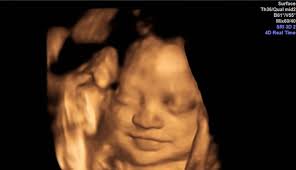

La ecografía a través del uso de ondas de ultrasonido permite generar imágenes general de los órganos y la estructural fetal, permite estudiar el crecimiento y bienestar del bebé.

Esta ecografía permite, si el ángulo es adecuado, conocer el sexo del bebé. Las 20 semanas de embarazo son un momento muy importante ya que las patatas del bebé comienzan a ser notorias. Las ecografías en el embarazo. Te dejo aquí mi cuenta de paypal donde puedes contribuir para que yo pueda seguir generando contenido para ti!! Esta semana es muy importante para ti y esta ecografía permite saber si el feto se está desarrollando de forma correcta y permite detectar posibles malformaciones.

22 semanas de embarazo ecografia morfologica. ¡felicidades, ya has llegado al ecuador del embarazo! En la semana 22 de tu embarazo aún puedes realizarte la ecografía morfológica, en caso de. Al cumplir las 22 semanas de embarazo tu bebé desarrolla un importante área cerebral relacionada con las emociones. Para el quinto mes, lo más normal es que la madre. Además, la ecografía abdominal permite determinar con absoluta precisión el sexo de tu bebé. Ecografía 3d, 4d o 5d. Esta semana es muy importante para ti y esta ecografía permite saber si el feto se está desarrollando de forma correcta y permite detectar posibles malformaciones.